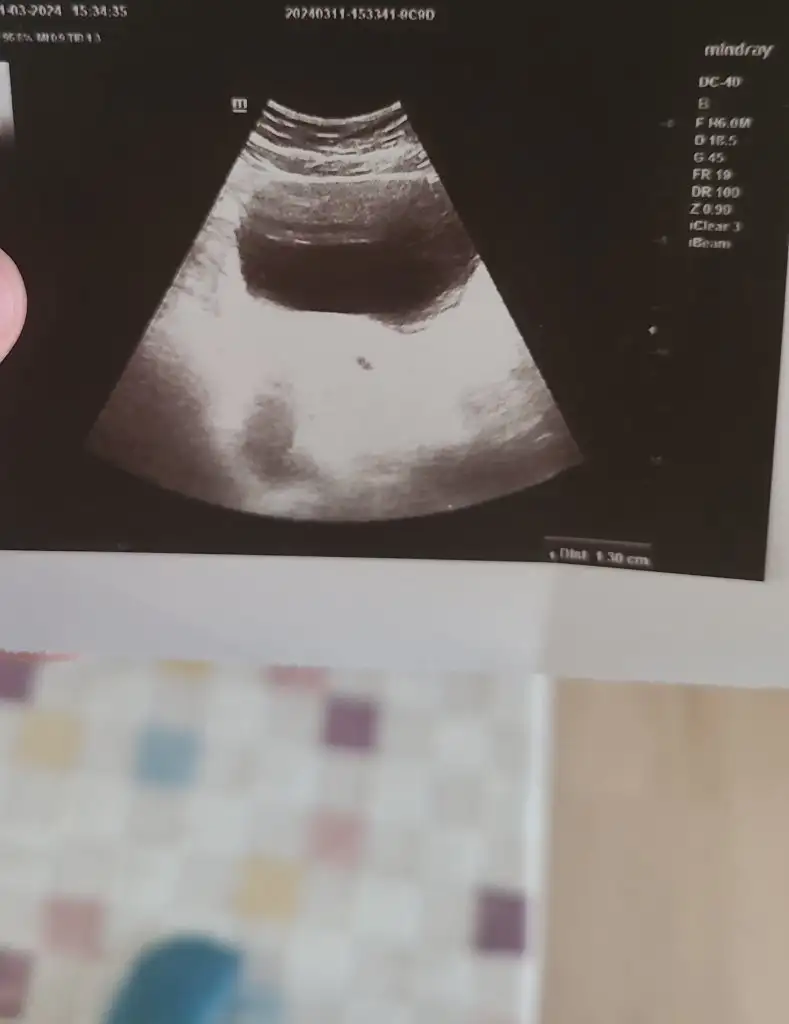

ay cok sevindim hayırlı olsun canım benimKızlar göbekten baktı çok şükür keseyi gördük yolk sac olusmus gayet düzenli gorunuyor kese dedi 16mm kese. Kalp atışı için 2 hafta sonra cagirdi

Kalp atışı içinde haftaya gel dediEki Görüntüle 3399784